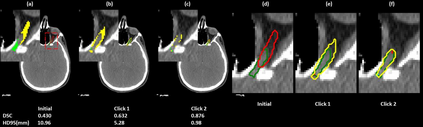

Automatic segmentation of anatomical structures is critical for many medical applications. However, the results are not always clinically acceptable and require tedious manual revision. Here, we present a novel concept called artificial intelligence assisted contour revision (AIACR) and demonstrate its feasibility. The proposed clinical workflow of AIACR is as follows given an initial contour that requires a clinicians revision, the clinician indicates where a large revision is needed, and a trained deep learning (DL) model takes this input to update the contour. This process repeats until a clinically acceptable contour is achieved. The DL model is designed to minimize the clinicians input at each iteration and to minimize the number of iterations needed to reach acceptance. In this proof-of-concept study, we demonstrated the concept on 2D axial images of three head-and-neck cancer datasets, with the clinicians input at each iteration being one mouse click on the desired location of the contour segment. The performance of the model is quantified with Dice Similarity Coefficient (DSC) and 95th percentile of Hausdorff Distance (HD95). The average DSC/HD95 (mm) of the auto-generated initial contours were 0.82/4.3, 0.73/5.6 and 0.67/11.4 for three datasets, which were improved to 0.91/2.1, 0.86/2.4 and 0.86/4.7 with three mouse clicks, respectively. Each DL-based contour update requires around 20 ms. We proposed a novel AIACR concept that uses DL models to assist clinicians in revising contours in an efficient and effective way, and we demonstrated its feasibility by using 2D axial CT images from three head-and-neck cancer datasets.